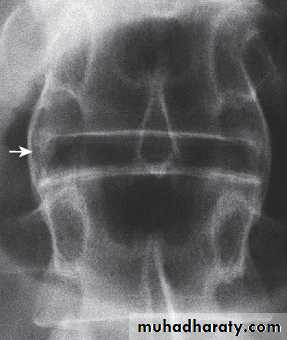

Lateral thoracolumbar spine Xrays may show anterior ‘squaring’ of vertebrae due to erosion and sclerosis of the anterior corners and periostitis of the waist.

Bridging syndesmophytes may also be seen. These are areas of calcification that follow the outermost fibres of the annulus

Investigations

In advanced disease, ossification of the anterior longitudinal ligament and facet joint fusion may also be visible. The combination of these features may result in the typical ‘bamboo’ spine.